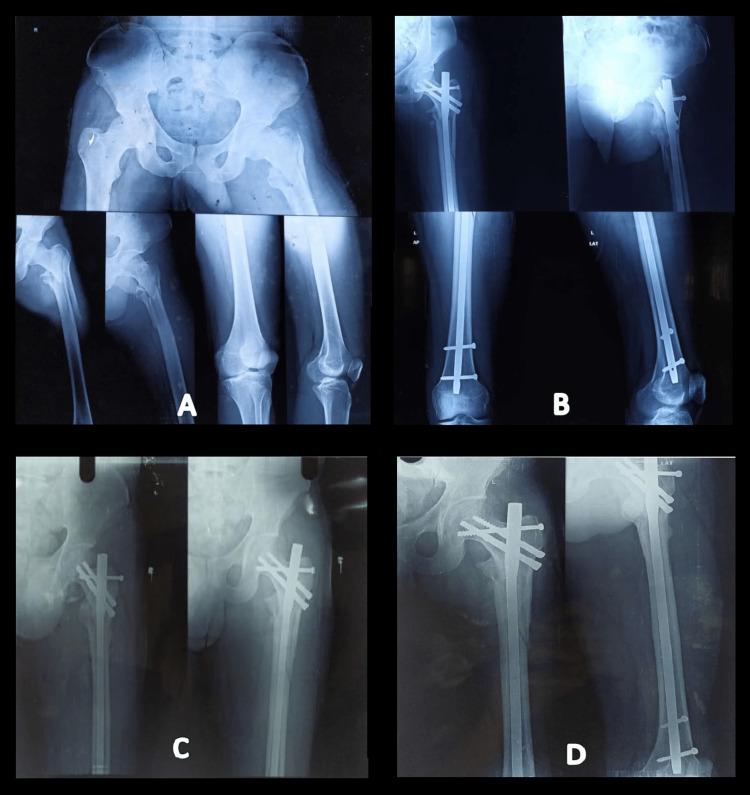

Introduction The proximal femoral nail (PFN) is a widely accepted fixation method for the management of unstable intertrochanteric fractures. Reconstructing the lateral trochanteric wall and ensuring the stability of the trochanteric fragments are considered to be essential for enhancing the prognosis of unstable intertrochanteric fractures. The aim of this study is to evaluate and compare the results of the management of unstable intertrochanteric fracture of the femur using PFN and the screw-augmented PFN (aPFN). Methods This prospective comparative study was undertaken from January 2020 to July 2021 and included 60 patients presenting with unstable intertrochanteric fractures (AO/OTA type 31-A2.2 and 31-A2.3) at a tertiary care teaching institute in northern India. The enrolled patients were randomly divided into two groups (group 1 and group 2) and were managed with screw-augmented PFN and PFN, respectively. Functional outcome was evaluated using the Salvati and Wilson score at the 12-month follow-up. SPSS version 24.0 (IBM Corp., Armonk, NY, USA) was used for statistical analysis. A p-value less than 0.05 was regarded as significant. Results The average time to union of the fractures in group 1 was 12.66 ± 1.68 weeks, while it was 13.47 ± 1.47 weeks in group 2 (p = 0.055). At the 12-month follow-up, the average functional outcome, as evaluated by Salvati and Wilson score, was 34 ± 2.40 in group 1, whereas it was 31.58 ± 4.4 in group 2; and the difference was observed to be statistically significant (p = 0.011). Group 1 had 28 patients (93.33%) with excellent to good results, while group 2 had 25 patients (83.33%) with excellent to good results. One patient in group 1 and five patients in group 2 had poor outcomes at the 12-month follow-up. Conclusion Screw-augmented PFN has better functional outcomes as compared to PFN alone for the management of unstable intertrochanteric fractures. Hence, in our opinion, screw augmentation of PFN may be the better fixation technique for most unstable intertrochanteric femur fractures.

引言 股骨近端髓内钉(PFN)是治疗不稳定型股骨转子间骨折广泛采用的固定方法。重建股骨外侧壁并确保转子间骨折块的稳定性被认为是改善不稳定型股骨转子间骨折预后的关键。本研究旨在评估和比较使用PFN与螺钉增强型PFN(aPFN)治疗不稳定型股骨转子间骨折的效果。方法 本前瞻性对照研究于2020年1月至2021年7月进行,纳入了印度北部一家三级医疗教学机构的60例不稳定型股骨转子间骨折患者(AO/OTA 31-A2.2和31-A2.3型)。将入选患者随机分为两组(第1组和第2组),分别采用螺钉增强型PFN和PFN进行治疗。在12个月随访时,采用Salvati和Wilson评分评估功能结果。使用SPSS 24.0版(美国纽约州阿蒙克市IBM公司)进行统计分析。p值小于0.05被视为具有统计学意义。结果 第1组骨折平均愈合时间为12.66±1.68周,而第2组为13.47±1.47周(p = 0.055)。在12个月随访时,根据Salvati和Wilson评分评估,第1组平均功能结果为34±2.40,而第2组为31.58±4.4;差异具有统计学意义(p = 0.011)。第1组有28例患者(93.33%)结果为优至良,而第2组有25例患者(83.33%)结果为优至良。在12个月随访时,第1组有1例患者、第2组有5例患者结果较差。结论 对于不稳定型股骨转子间骨折的治疗,螺钉增强型PFN比单纯PFN具有更好的功能结果。因此,我们认为,对于大多数不稳定型股骨转子间骨折,PFN的螺钉增强可能是更好的固定技术。